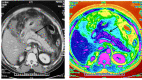

Improved insights into the pathophysiology of acute pancreatitis have paved the way for identification of distinct entities in the spectrum of the disease. The presence of necrotising inflammation limited to peripancreatic tissue with a normal appearance of pancreas is one such entity. This entity, described as extrapancreatic necrotising pancreatitis (EPN), is considered a less aggressive form of acute necrotising pancreatitis. This entity needs to be recognized precisely and managed accordingly among patients with acute pancreatitis. However, EPN has not been highlighted in the revised classification of acute pancreatitis. Here we report two patients with EPN with varied presentations and diverse management and outcome.